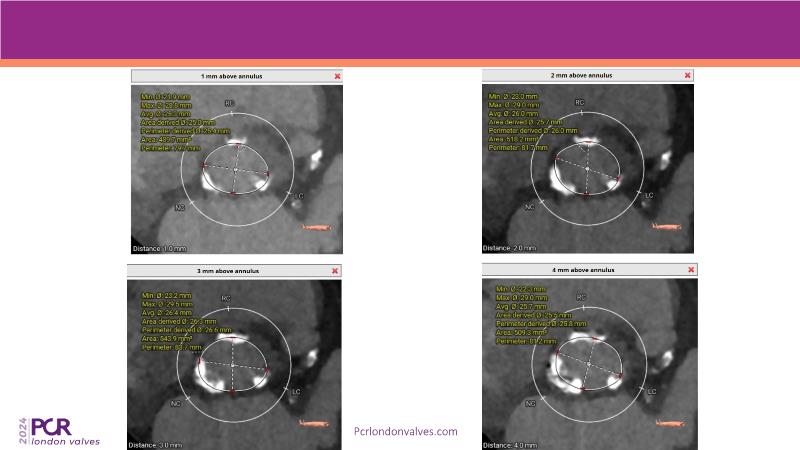

- To learn from the experts best-in-the-class TAVI practice: pre-procedural (Imaging, sizing rationale, treatment strategy), procedural tips and tricks and post-procedural management